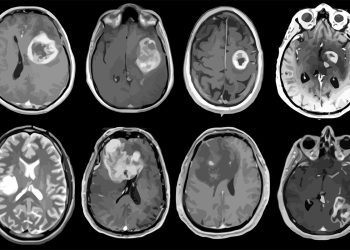

New study finds brain cancer surge in gen X

A new study says that people born between 1965 and 1980, called Gen X, are getting ...